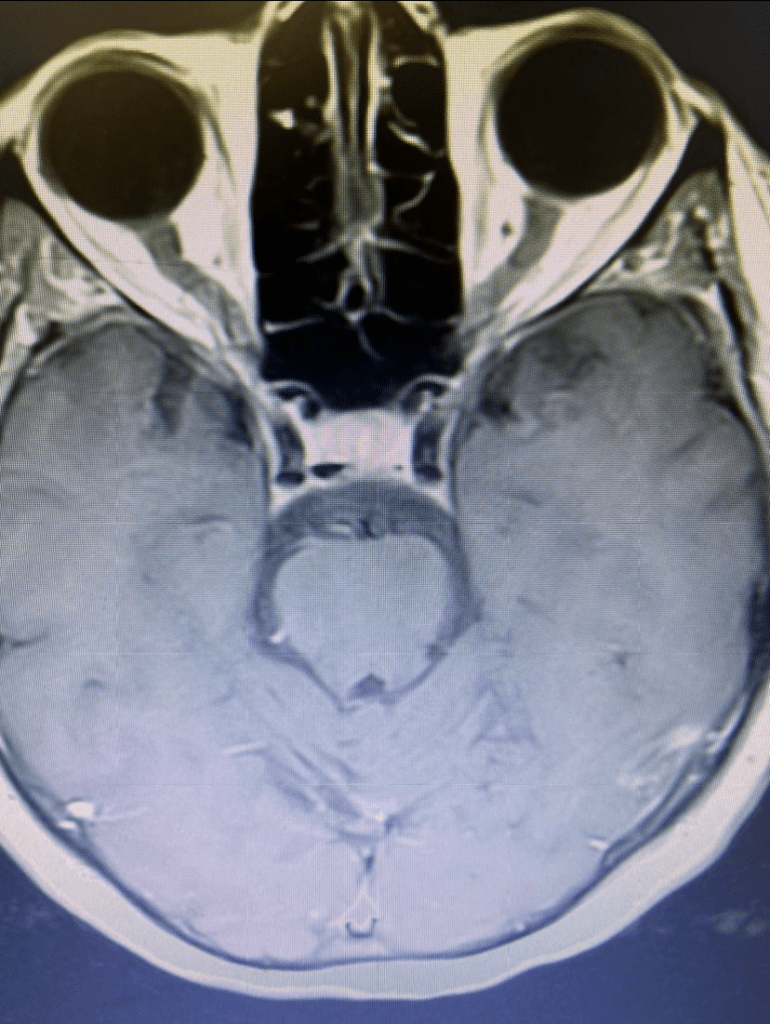

She returned for a follow up visit 19 years after the Gamma Knife treatment just to check up on things. She felt well and was neurologically intact. MRI and CTA of the brain were performed, which demonstrated complete obliteration of the AVM.

Figure 2B. Axial T2 MRI.